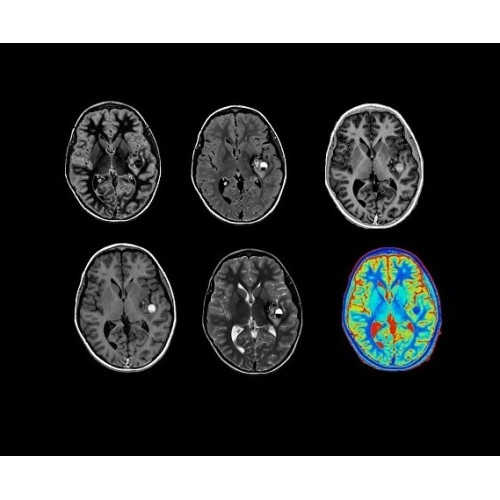

• ImageWorks — повысит производительность МРТ благодаря визуализации высокого качества с MAGIC, четкими результатами пост-процессинга с READYView.

• 48-канальная катушка TDI для головы, входящая в базовую комплектацию SIGNA Architect, обеспечивает феноменальную производительность с учетом особенностей каждого пациента. Благодаря гибкому и универсальному дизайну, высокому соотношению сигнал/шум и передовым технологиям визуализации, таким как HyperWorks, учитываются потребности подавляющего большинства пациентов.